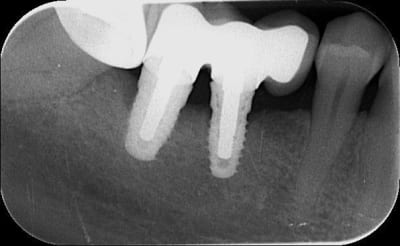

Voici trois Rx : cratère ou pas ? quel taux d'échec à 5 ans (tout les implants), ce sont les mêmes : 3I plateforme plate, deux temps chir, pas de plateform switching, pilier vissé prothèse scellée, 3 mois d'OI.

Crat 1 k8pnfh - Eugenol

Crat 2 ra8vyw - Eugenol

Crat 3 hpsffn - Eugenol

j'ai posé deux easy avec le biseau enfoui dans l'os. A 3 mois, pose des piliers de cicatrisation et un mois plus tard pose de la prothèse.

manifestement l'os ne reste pas en place à ce niveau

je prendrai un cliché dans 3 mois pour évaluer ce qu'il advient de la zone mésiale du col de l'implant distal.

46 47 xvjblf - Eugenol

46 47 pose kiaay7 - Eugenol